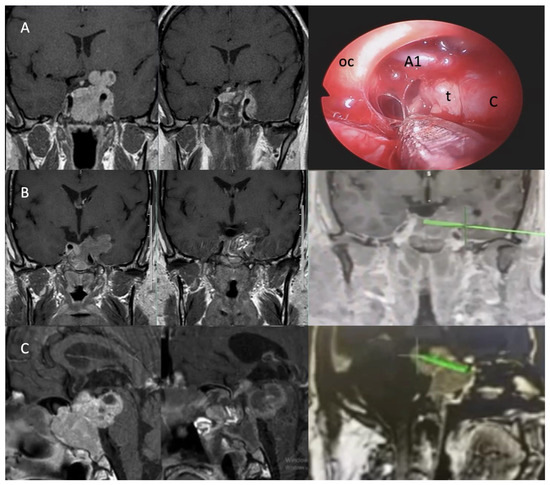

- Yilmaz, E.; Uzuner, A.; Ceylan, E.C.; Yildirim, P.; Duman Ozturk, S.; Emengen, A.; Gokbel, A.; Caklili, M.; Cabuk, B.; Anik, I.; et al. Operative Nuances of Capsular Dissection Techniques and Capsule Morphology in Pituitary Adenomas: Past 1-Year Case Experiences of a Tertiary Center. Oper. Neurosurg. 2024, 27, 681–689. [Google Scholar] [CrossRef]